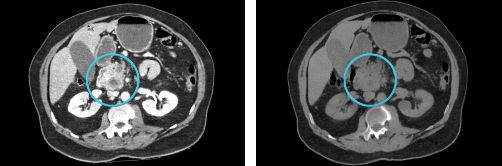

GSI MAR

Left: 40 keV; Right: 40 keV with GSI MAR. GSI Metal Artifact Reduction (GSI MAR) is a dual energy metal artifact reduction algorithm designed to reveal anatomic details obscured by metal artifacts. GSI MAR benefits for radiation oncology: reduced artifacts for more productive target delineation and dose calculation.

GSI-MAR